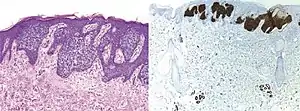

Comparison H&E stain (left) with BerEP4 immunohistochemistry staining (right) on a pathological section having BCC with squamous cell metaplasia. Only BCC cells are stained with BerEP4.[1]